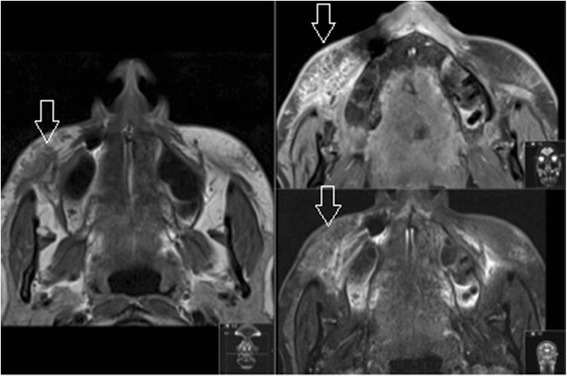

Fig. 3.

Silicone dermal filler in the right infraorbital triangle (open arrow) as seen on axial MRI (T1, T1FS with gadolinium, T2FS). Note how the free silicone oil drops behave like fat on MRI, including a intermediate to low signal on fat suppressed sequences

For example, when a patient is unsatisfied with the result of a cosmetic injectable filling procedure, MRI could be used to provide an objective evaluation of fullness and symmetry. While scarring, which demonstrates a low signal on T1 weighted images and directly impacts the symmetry of dermal fillers, it does not hamper the correct identification of substance or the radiologist’s ability to assess the distribution of substance. If overfilling is confirmed (Fig. 4), and hyaluronic acid is determined to be the culprit, a simple injection of hyaluronidase can reverse the unwanted outcome [14]. In cases of complications involving an unknown product, imaging can help to establish the identity and guide the approach to treatment. When a granuloma arises from permanent filler (Fig. 5), treatment may require administration of 5-fluoruracil or allopurinol; otherwise, steroids and imiquimod may be used [15, 16]. This further underscores the importance of identification of the precise substance prior to initiating therapy as regards patients’ treatment outcomes.

Fig. 4.

Hyaluronic acid dermal filler in the lower infraorbital triangles (open arrows) on coronal MRI (T2FS)